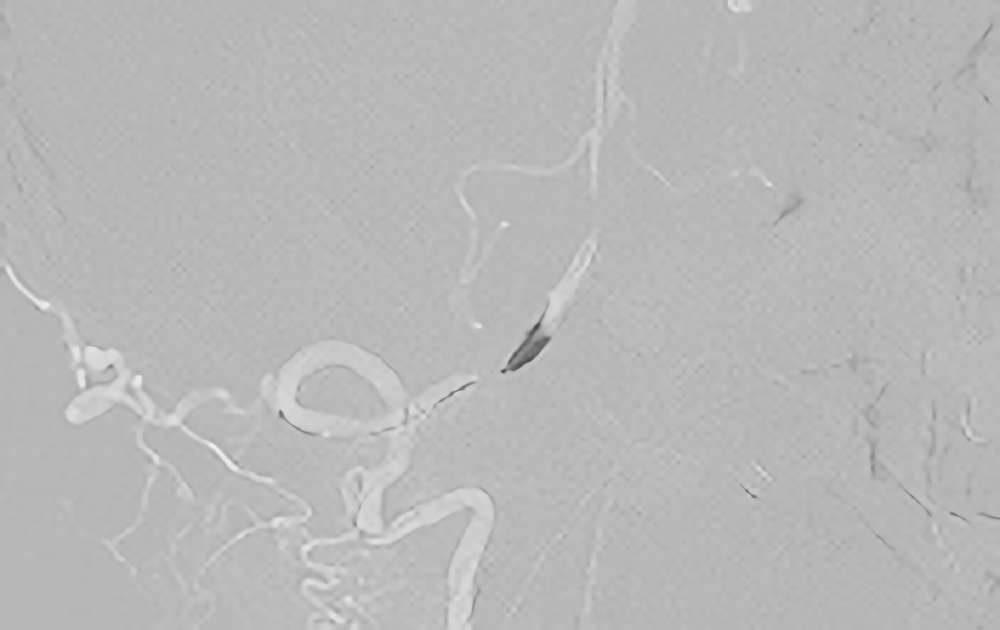

'21年5月

左解離性椎骨動脈瘤

50代

院内外来

No.1046 手術前

No.1046 手術中

No.1046 手術後